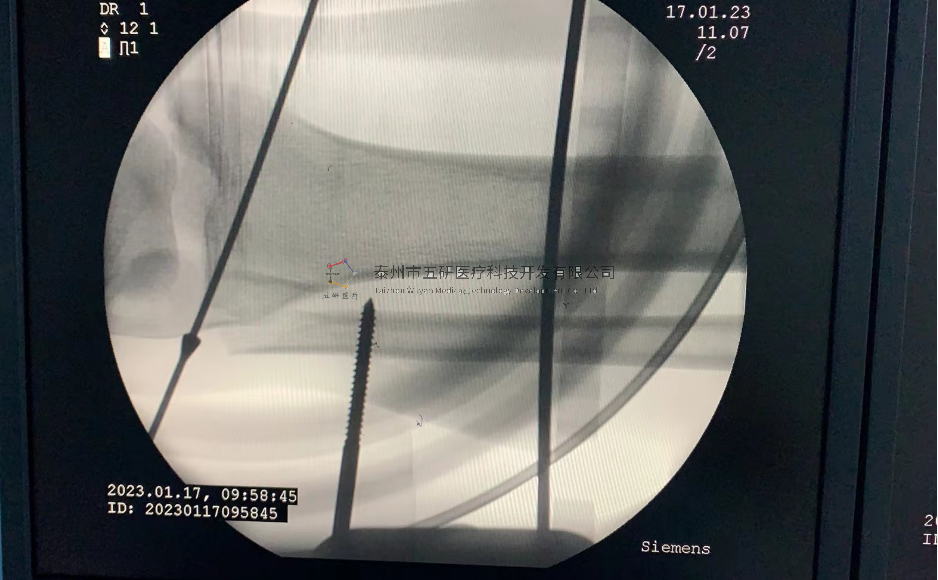

// 下肢骨折

【所屬科室】中國中醫(yī)科學(xué)院望京醫(yī)院創(chuàng)一科

【基本資料】患者,男,65歲

【患者情況】脛骨遠端骨折伴腓骨骨折

【影像圖片—術(shù)前】

【影像圖片—術(shù)后】